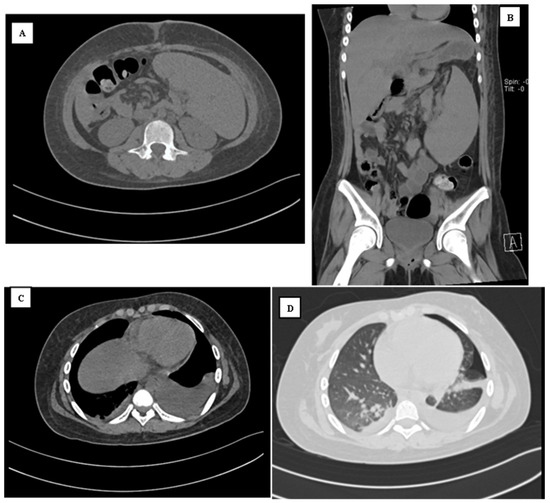

3. Case Presentation